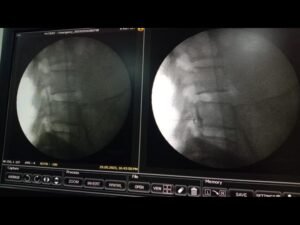

- Epidural Steroid Injections (ESIs): In cases of severe or persistent pain, an ESI may be recommended. This procedure involves injecting a corticosteroid medication directly into the affected area to reduce inflammation and alleviate pain.